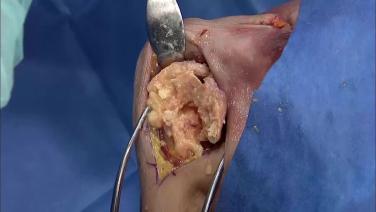

Revision Shoulder Arthroplasty Extraction Instrumentation: Case 2 with George Bal MD

Revision Shoulder Arthroplasty Extraction Instrumentation: Case 1 with George Bal MD